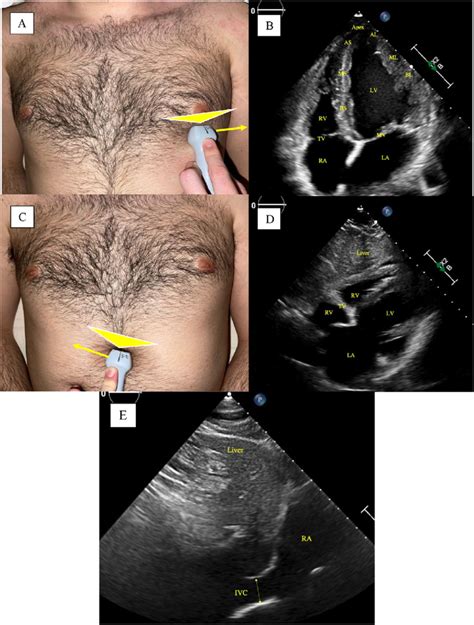

Mastering The 5-Chamber Echo View: Probe Placement Guide

Alright team, let’s get down to the nitty-gritty of probe placement for that awesome 5-chamber view . This is where the magic happens, guys! You’ll typically want to start at the apical window . Think of the apex of the heart – that’s your target zone. Position the transducer at the left lateral chest wall , usually between the fifth and sixth intercostal spaces . Sometimes, you might need to go a little higher or lower, or more medially or laterally, depending on your patient’s body habitus. The key here is to aim the transducer towards the patient’s right shoulder . This orientation is super important because it allows the ultrasound beam to pass through the heart without being significantly blocked by the lungs or ribs. Imagine you’re trying to get a direct line of sight to the heart’s core. Now, the initial placement might give you a 4-chamber view. That’s a great starting point! From there, you’ll need to make subtle adjustments. The goal is to rotate the transducer slightly counter-clockwise (think of the indicator dot on the probe pointing towards the patient’s left axilla) while maintaining that apical position. This subtle rotation is what brings the aortic valve into view, effectively transforming your 4-chamber view into the coveted 5-chamber view. You’re essentially peeking over the left atrium to get a glimpse of the aortic outflow tract. Remember, you’re looking for a clear image of the left ventricle, left atrium, mitral valve, and the aortic valve, all in the same plane. The interventricular septum should be on your left, and the left atrial wall on your right. The aortic valve will be seen superiorly and slightly to the left of the mitral valve. Fine-tuning is everything. Small tilts and shifts can make a huge difference in image quality. Don’t be afraid to gently fan the transducer or adjust the depth and gain controls to optimize what you’re seeing. The goal is a symmetrical-looking left ventricle, with well-defined walls and clear visualization of all four chambers and the aortic valve. Practice makes perfect, so keep trying different angles and positions until it feels intuitive. You’ll know you’ve got it when you can see the mitral valve leaflets opening and closing, and the aortic valve opening during systole. This view is crucial for assessing mitral regurgitation, aortic stenosis, and the overall function of the left side of the heart. It’s the integration of anatomical understanding with hands-on manipulation that truly elevates your echocardiography skills. Patient positioning can also play a role; a left lateral decubitus position often facilitates better apical access. However, always adapt to the patient’s ability to tolerate different positions. The depth setting on the ultrasound machine is critical; you want to ensure the entire heart is displayed without excessive surrounding tissue. Similarly, the gain settings need careful adjustment to differentiate between the endocardium, myocardium, and blood pool, avoiding both under-gaining (poor visualization) and over-gaining (flash artifacts or loss of detail). Patience and persistence are your best friends here. It might take a few tries, or even a few minutes, to achieve the optimal view, especially in patients with certain body types or lung disease that can impede ultrasound transmission.